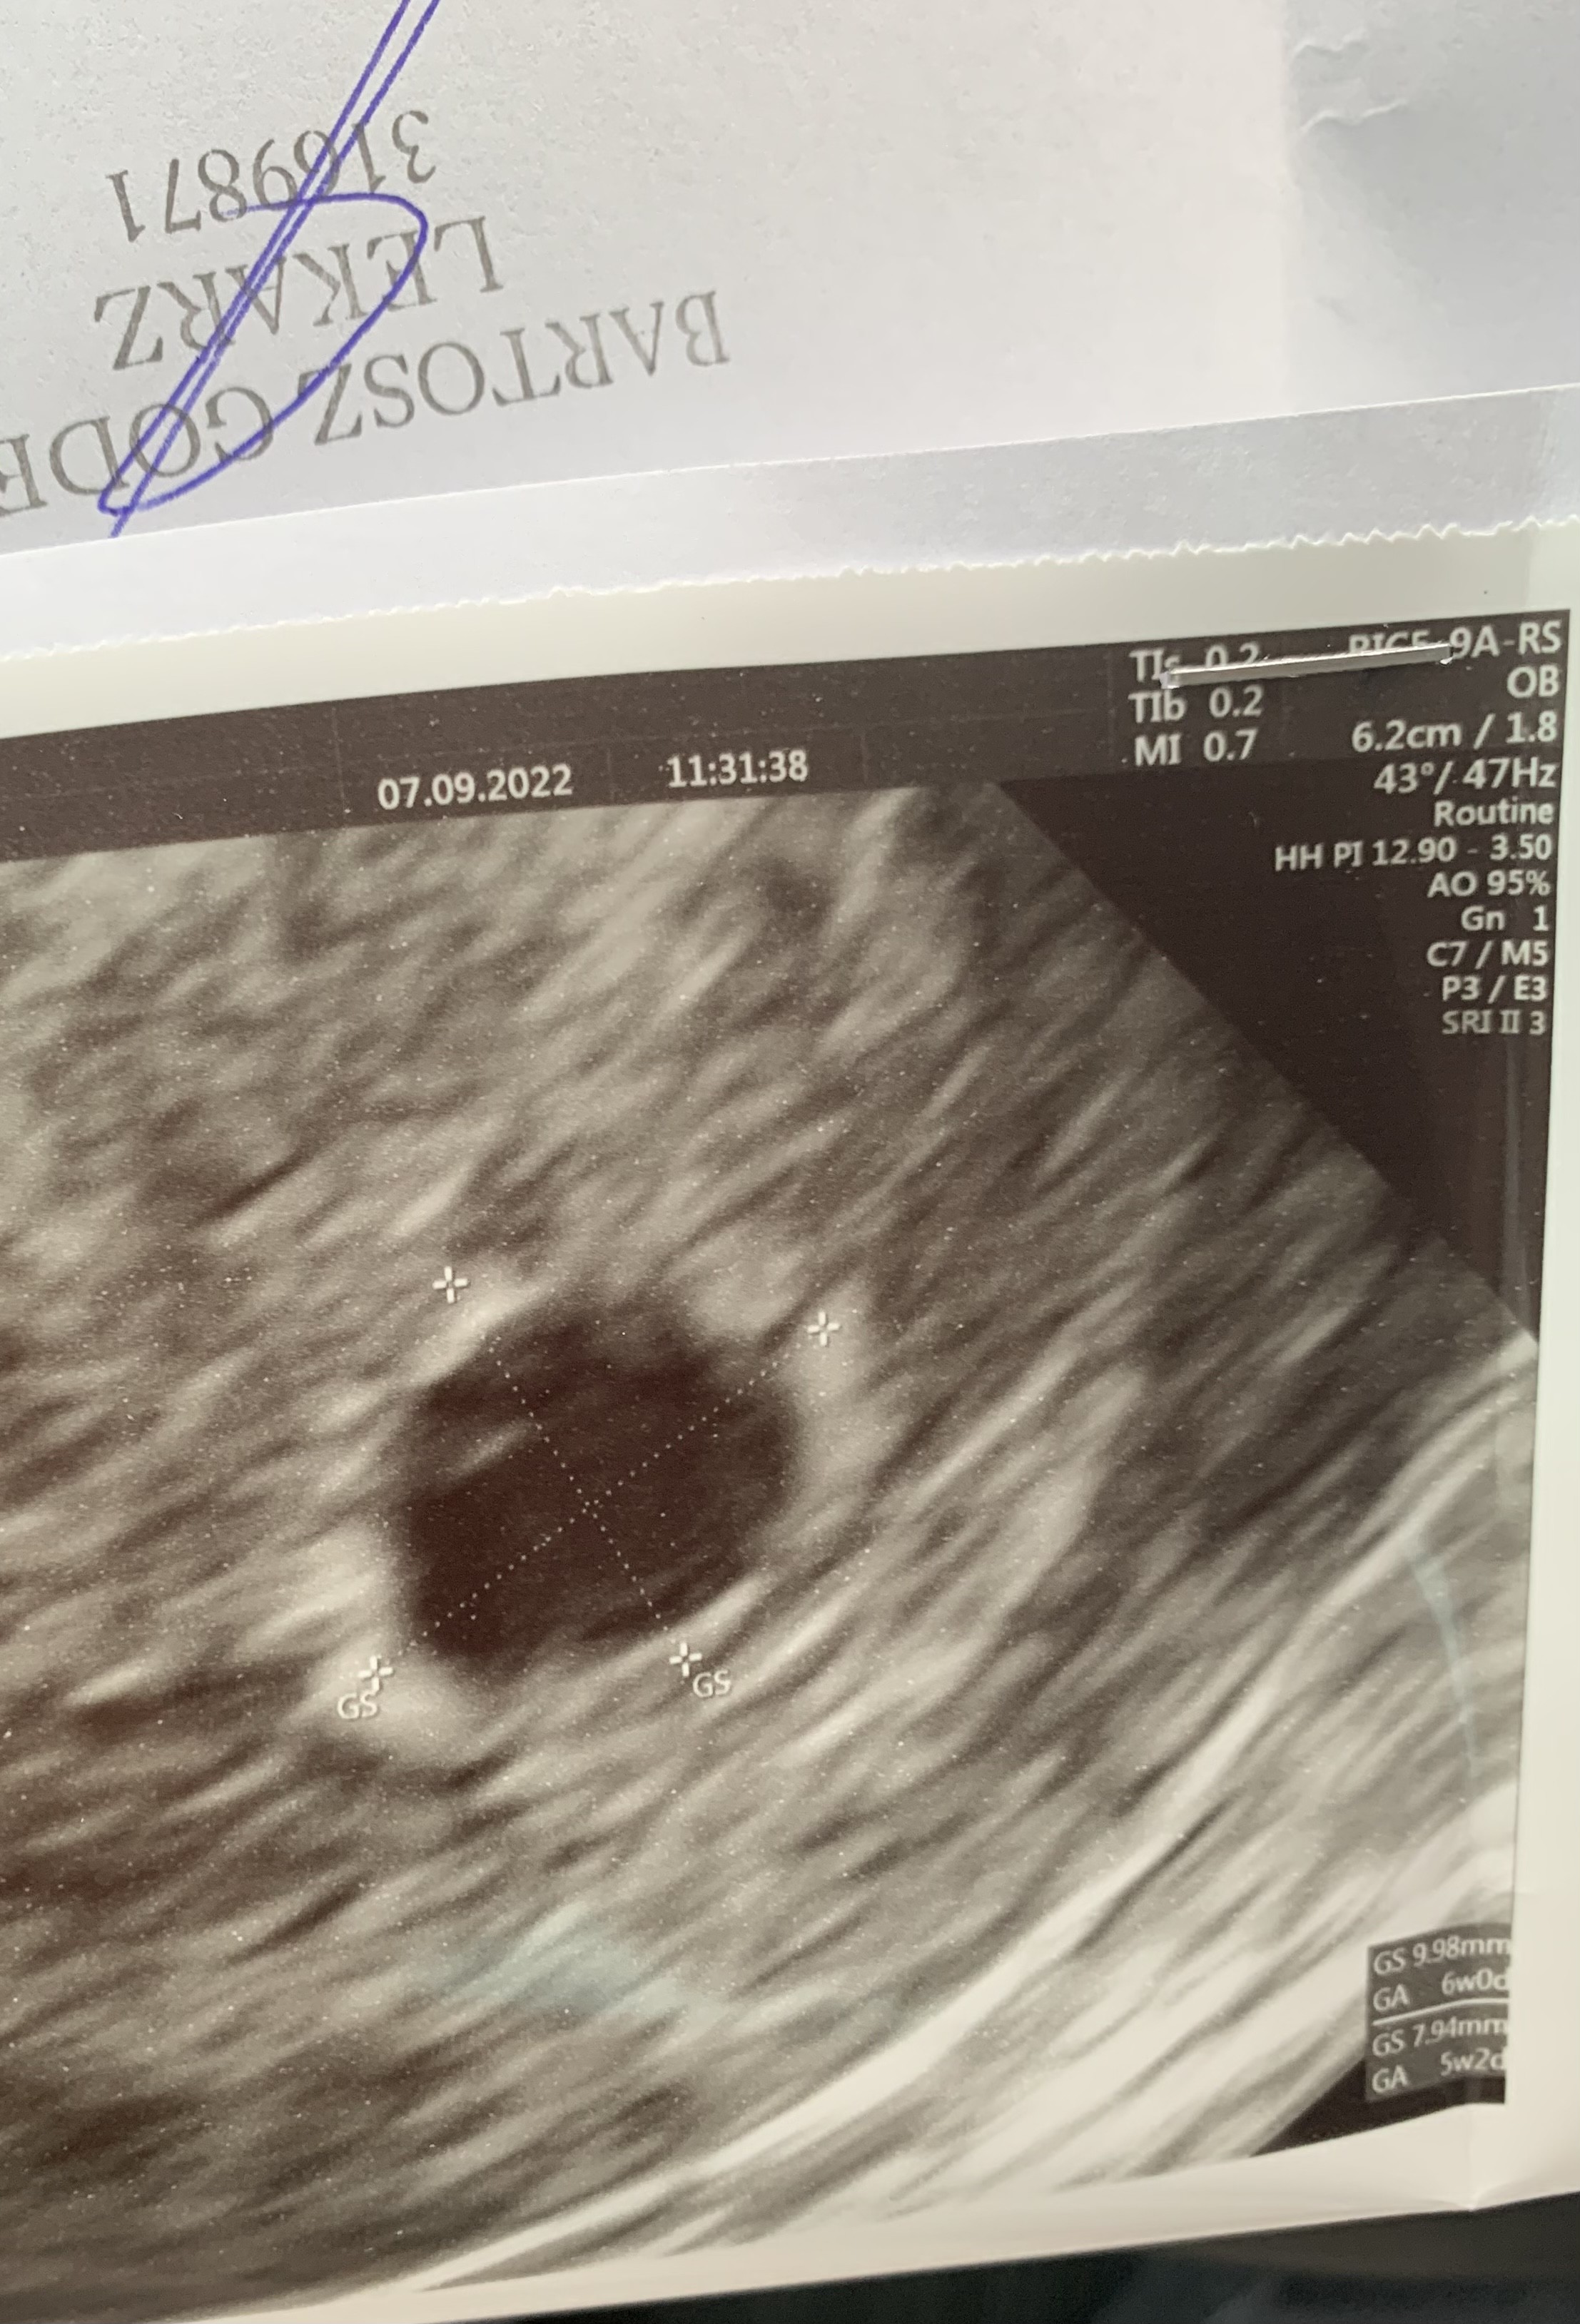

Dziewczyny 7 wrześni byłam na pierwszym usg. W macicy widoczny pęcherzyk ciążowy o wym 9,98 x 7.94. Brak pęcherzyka żółtkowego. Następne usg 19 września. Ostatnia miesiączka 25 lipca. Przeważnie cykle 31-33 dni. Myślicie, że jest szansa że pijawi się jeszcze pęcgerzyk żółtkowy i zarodek. Na usg widać w pęcherzyku jakąś dziwna smuge. Beta w dniu usg ponad 4600

• 4026ECFA-9E68-4D97-9057-5BADEE71E8E7.jpeg

4026ECFA-9E68-4D97-9057-5BADEE71E8E7.jpeg

1 MB · Wyświetleń: 127